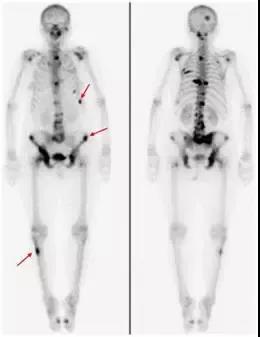

5.全身核素骨显像(ECT):

用一种对人体无害的放射性同位素注入血液中,由于这种同位素与骨头的代谢和血液循环是密切相关的,一旦发生了骨的破坏就会发现破坏处的浓聚,通过成像就能看到病变部位及数量。一旦前列腺癌诊断确立,建议进行全身核素骨显像检查,用于判断前列腺癌是否出现了骨转移。